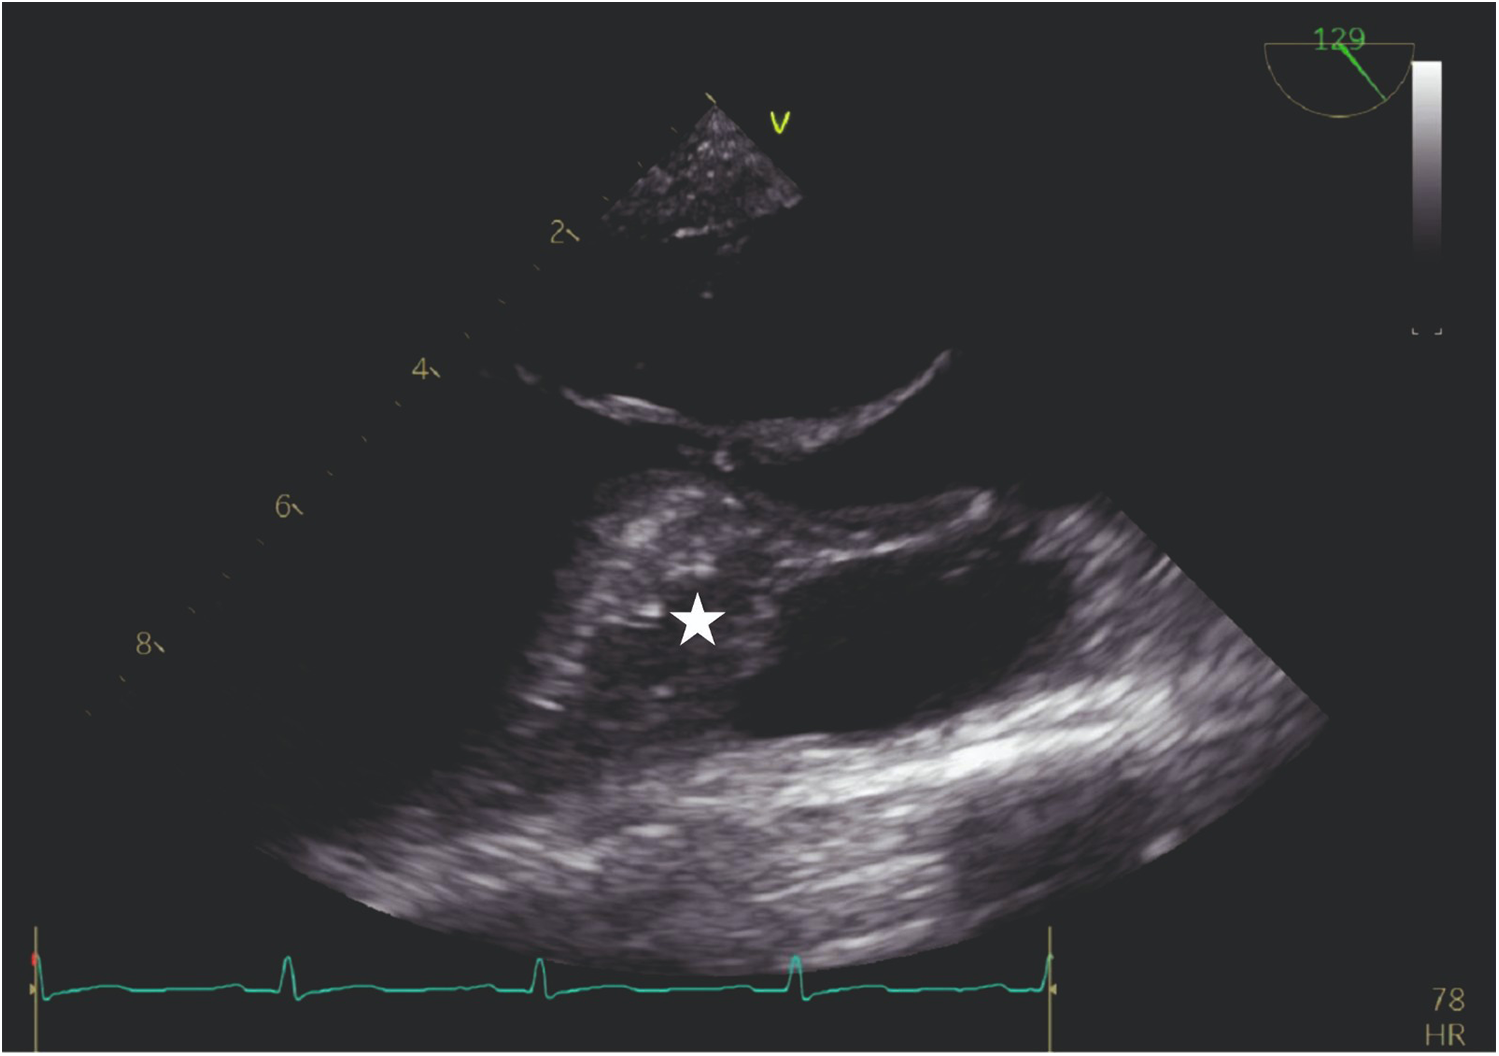

Figure 3

TEE view: the interventricular septum prior to the injection of cocktail fluid.

Our agitated contrast substance included cocktail fluid (agitated 5 mL of saline plus 0.5 mL blood of the patient, shaken in a three-way-stopcock (Figure 2). In TEE, the basal interventricular septum was compared with the same views recorded at baseline. Finally, we observed an enhancement of the basal septum (Figures 3, 4). Then, 1–2 mL of ethanol (absolute alcohol 96%–99%) was injected into the TSAB. We injected alcohol into the target perforatory artery in a step-by-step manner to observe a reduction in mitral regurgitation and QT prolongation at electrocardiographic monitorization (initially, 0.5 mL alcohol, then by increasing the dosage up to 3 mL). Two of the 14 patients had a single perforator artery with a double branch. In these patients, we performed superselective septal catheterization. Then, we administered contrast agents to both branches. Next, we found the correct branch feeding basal interventricular septum.